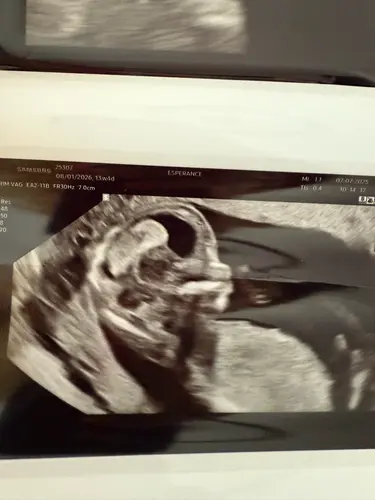

Dan gaan we hier verder 馃槂 wat denken jullie aan de Skull te zien, jongen/meisje ?馃挋馃┓

Dan gaan we hier verder 馃槂 wat denken jullie aan de Skull te zien, jongen/m ...